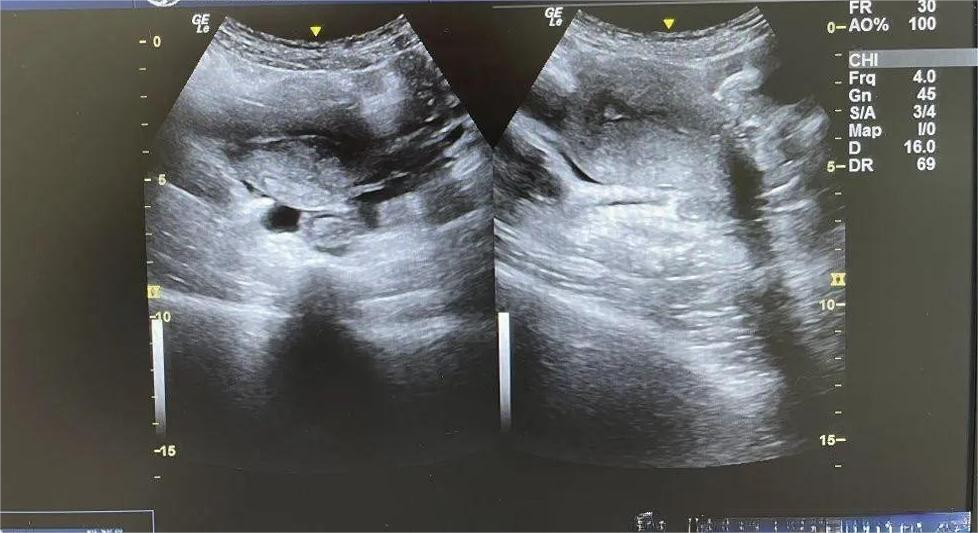

B超引导的人流手术可以更好的定位孕囊的位置,能够使手术更加的安全和有效,可以减少手术中患者的疼痛,也大大地减少了手术的并发症。B超引导提高了手术成功的准确性,减少潜在的手术风险,使人流手术变得相对的安全和简单。

一、什么是超声引导下可视无痛人流术?

超声引导下可视无痛人流术是通过短效麻醉药使患者处于睡眠状态,在超声引导下施行的无痛人工流产术,它能最大限度地保障女性朋友的舒适、安全、无痛。